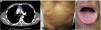

He had a two-week history of pruritic skin rash showing multiple papular keratotic lesions located on the extremities and trunk (Fig. 1 a, b). He also had a marked periorbital and peribuccal hyperpigmented lesions, dryness and scaling of the lips and painful eroded whitish reticulated lesions involving the tongue and oral mucosa. Progressive dysphagia and persistent diarrhoea were also present. No blood transfusions or solid-organ transplantation were performed before the onset of the lesions. (Fig. 2 a, d, g).

CT showing thymoma tumor mass and lung metástasis (a). Low-power view of thymoma needle biopsy with a predominant small cell population, H-E x20 (b). Higher magnification showing cytokeratin-positive larger epithelial tumor cells and numerous lymphocytes, AE1-AE3, x400 (c).

Skin rash (d). Epidermal hyperplasia with numerous apoptotic keratinocytes, H-E x200 (e). High power showing apoptotic keratinocytes with satellite lymphocytes, H-E x400 (f).

Oral lesions (g). Scanning magnification showing bullous lesion with extensive basal cell damage, H-E x20 (h). The roof shows apoptotic keratinocytes with satellite lymphocytes, H-E x400 (i).